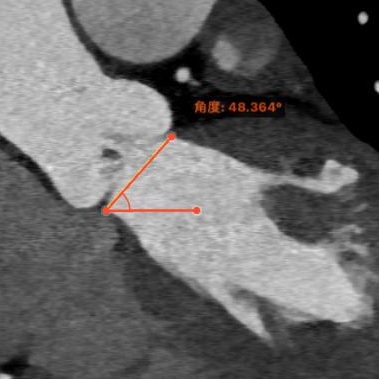

横位心:48°